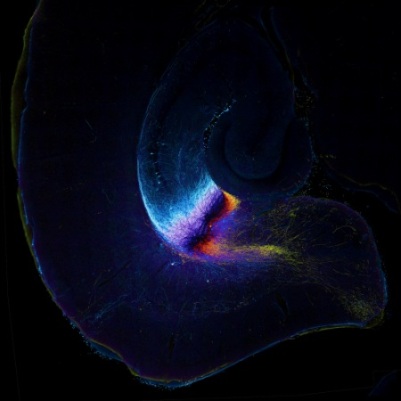

Sjoerd Vos (Universitair Medisch Centrum Utrecht) – The Intergalactic Brain.

[kliktv nr=3]